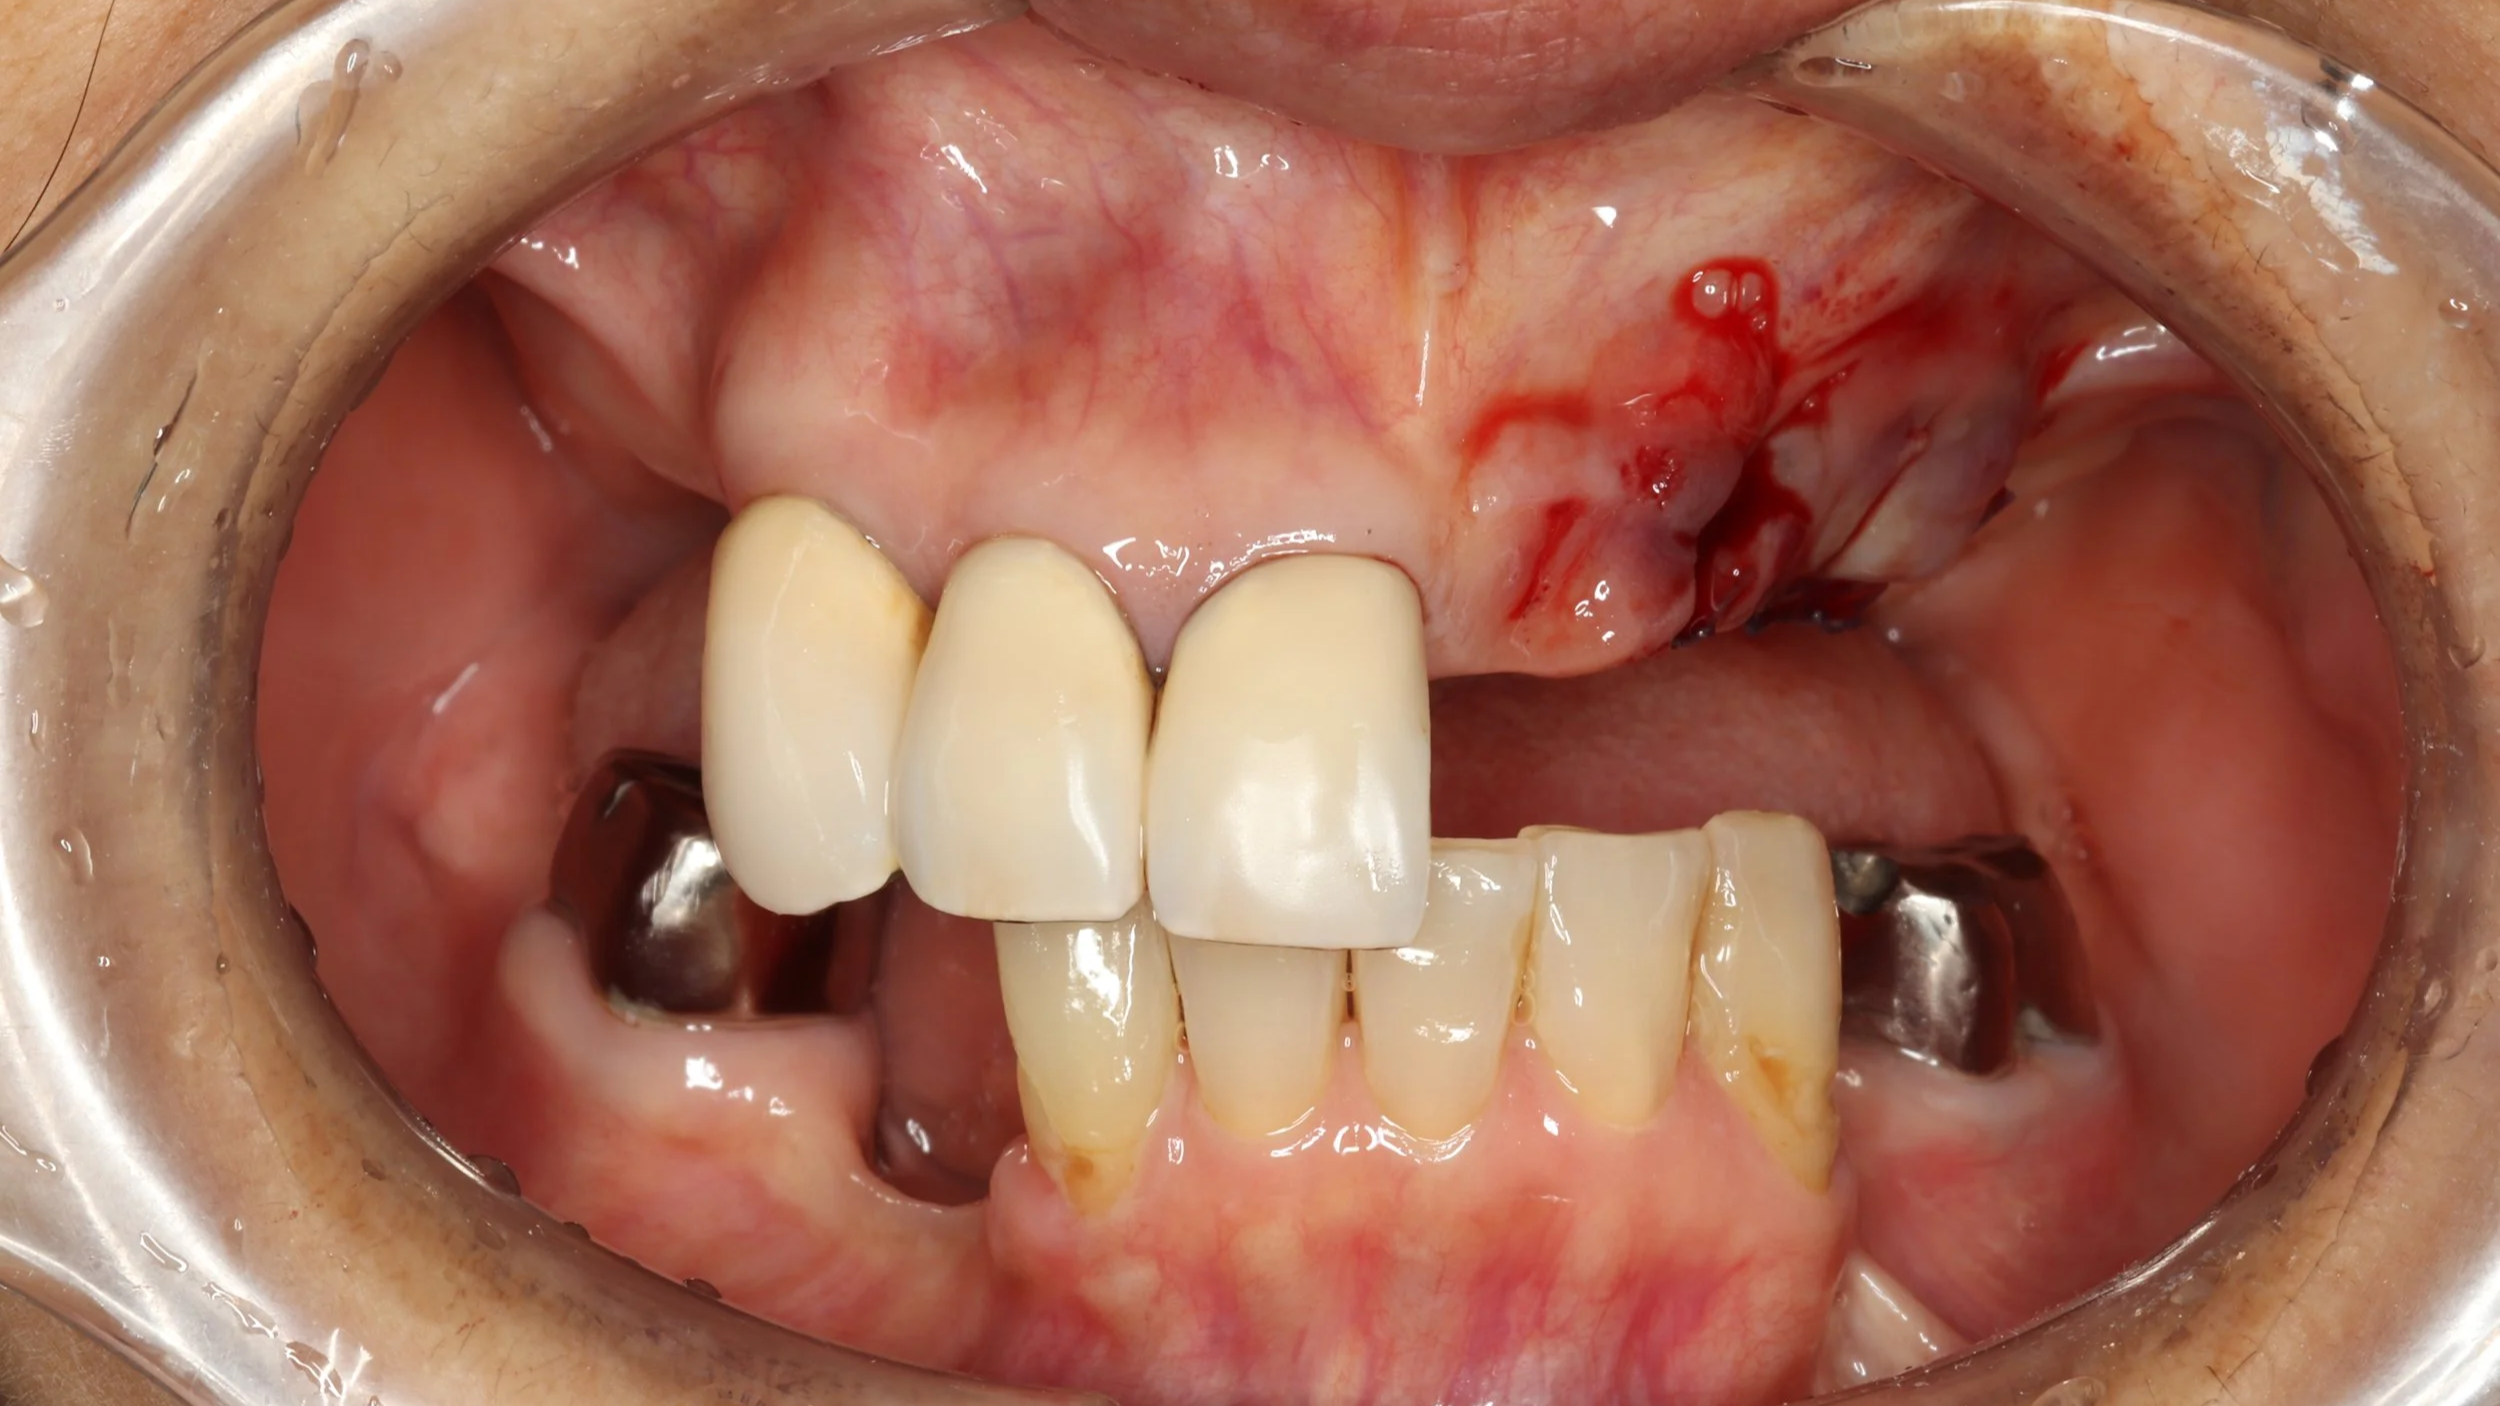

1回目

他院で入れ歯を作ったけど あまり使わなかったことで、前歯が折れてグラグラな状態でしたが、デジタルでの型取りにて、製作開始。

2回目

連結されている前歯を切断するとともに、折れた根の抜歯を行い、その後デジタルデンチャーを装着し機能回復を開始しました。